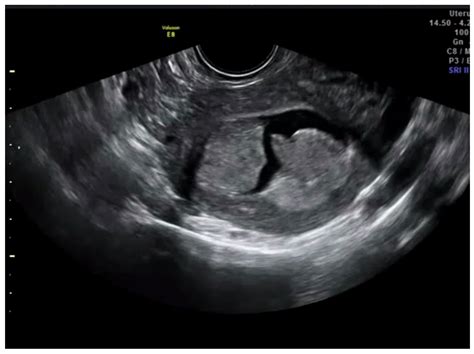

The endometrium is the inner lining of the uterus, which naturally thickens and sheds during a woman's reproductive years. In postmenopausal women, however, this lining should remain thin. When bleeding occurs after menopause, or if there is concern regarding uterine abnormalities, an Endometrial Cancer Ultrasound is typically the first line of defense. This imaging technique uses high-frequency sound waves to create detailed images of the uterus, allowing radiologists and gynecologists to measure the thickness of the endometrium, often referred to as the endometrial stripe.

There are two primary types of ultrasound used to examine the endometrium: transabdominal and transvaginal. For the best visualization of the uterus, the transvaginal approach is generally preferred.

• Transvaginal Ultrasound: A specialized, slim transducer is inserted into the vagina. This provides much higher resolution images, particularly of the endometrium, because the transducer is positioned closer to the uterus.

Interpreting Ultrasound Results: Measuring the Endometrial Stripe

The primary metric used during an Endometrial Cancer Ultrasound is the thickness of the endometrial stripe. Doctors measure the thickest part of the lining in a longitudinal plane. While thresholds can vary based on individual risk factors, general guidelines exist to help guide clinical decision-making.